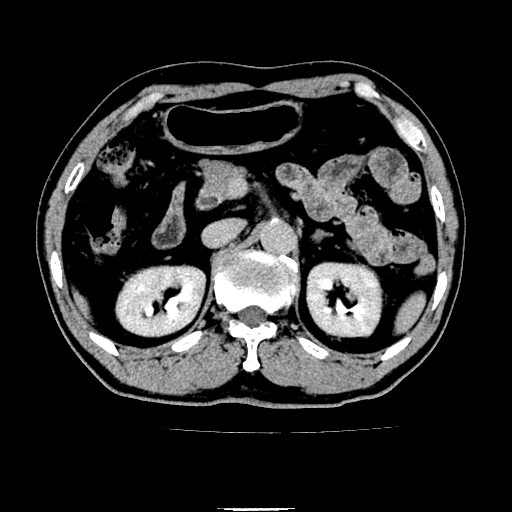

以下是引用chenqiong在2010-3-25 20:56:00的发言:[br]1、胆囊炎,胆囊息肉[br]2、肝内胆管及胆总管扩张,胆总管下端结石[br]3、十二指肠乳头旁憩室

以下是引用zxl51642在2010-3-26 10:47:00的发言:[br]胆囊炎,胆囊息肉,胆总管扩张,但未看到明显肿块,肝内胆管扩张不像恶性,炎性狭窄或阴性结石可能吧,建议mrcp,右肾小囊肿